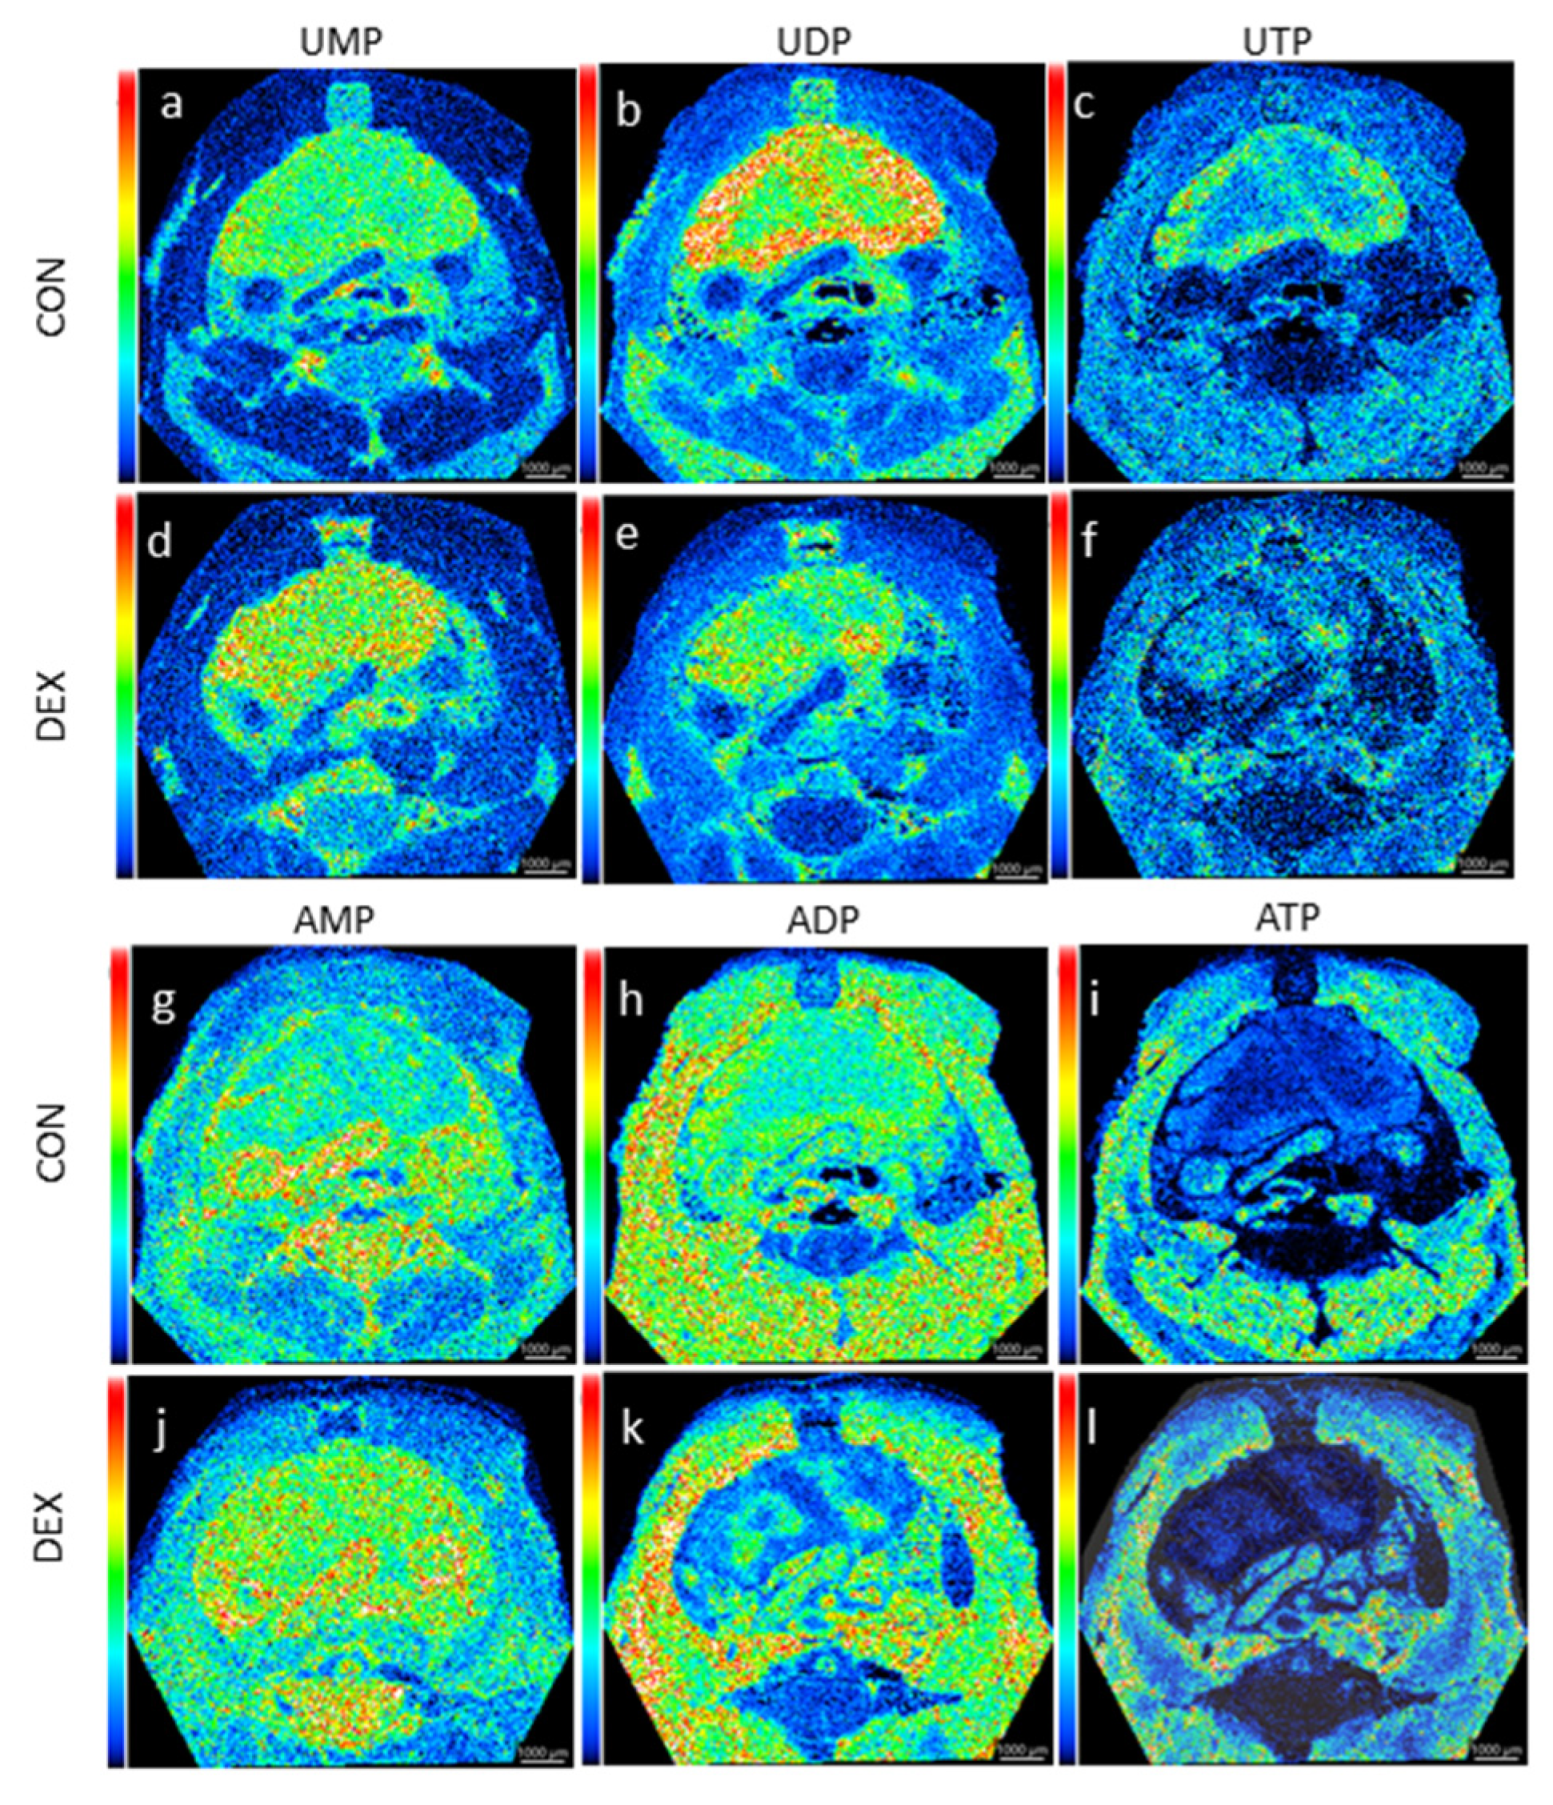

6.3. Dexamethasone Alters Global Energy Status of the Mice In Vivo